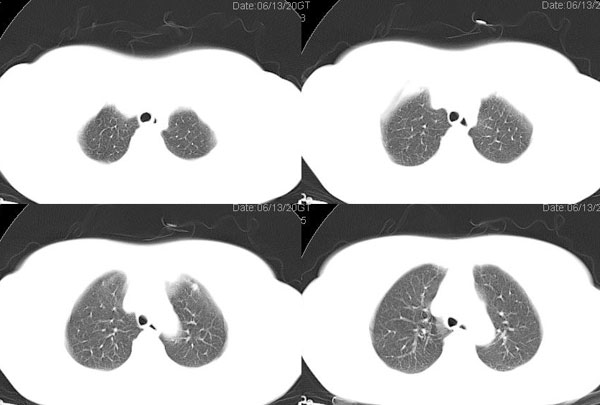

以下是引用jiangjing在2006-8-29 20:10:00的发言:[br]x线平片:左肺中野可见一约15mm*15mm的高密度影.[br] ct图像所见: 左肺下叶背段可见一直径约2.0cm类圆形肿块影,边缘模糊,有浅分叶,肿块周边可见沙粒样高密度影,肿块内可见空泡征,气管主支气管通畅,纵隔内未见明显肿大淋巴结影。 [br]诊断意见:左肺下叶背段可见一直径约2.0cm类圆形肿块影,肿块周边可见沙粒样高密度影,再结合2型糖尿病8年。多考虑:结核瘤。后经化验 ppd实验(++)[br]支持版主的考虑,病灶周围可见小点结影可疑卫星灶,但不完全除外肿瘤。建议增强及穿刺活检